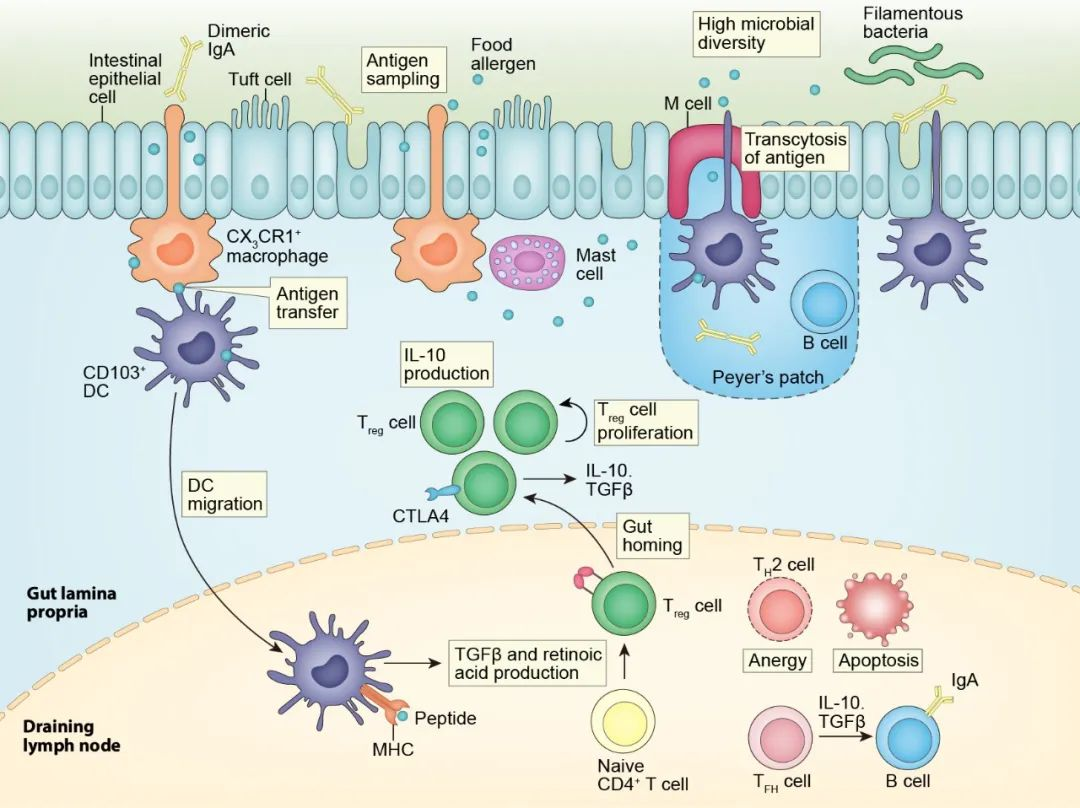

论文插图设计

滑动查看更多 点击查看大图